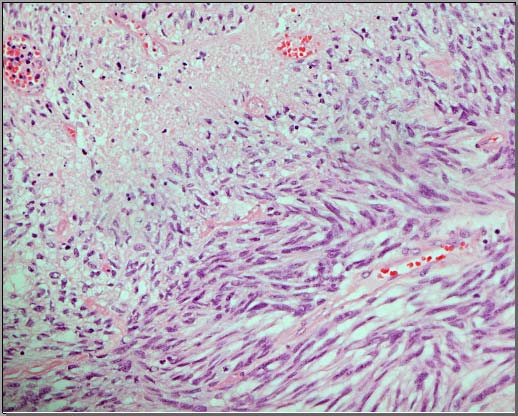

The results obtained by the ten participating pathologists and the two neuropathologists are summarized in Table 1. The kappa score for interobserver agreement between the ten anatomical pathologists was 0.53 (95 % CI for free-marginal kappa [0.32, 0.74]) with an overall agreement percent of 68.44%. The kappa score for interobserver agreement between the two neuropathologists was 0.55 (95 % CI for free-marginal kappa 0.1, and 1) with an overall agreement percent of 70%. Both kappa scores are in keeping with above chance "intermediate to good" agreement (7). The cases that showed 100% agreement were three cases. Two cases were WHO grade I. The third case was WHO grade II (Case 2, Figure 1). The latter was the only meningioma from the selected cases that showed focal necrosis. Another five cases were graded as either WHO grade I or WHO grade II by the reviewers. These cases were showing a variable degree of small cell change, lack of pattern, and cellularity (Figure 2).These cases did not show features of necrosis or prominent nucleoli. Two cases (Cases 8 and 9) were labelled as WHO grade II by the majority of the reviewers. However, in each one of them, two reviewers labelled them as WHO grade III (Figure 3). In their opinion, the reason for such designation was the focal presence of sarcomatoid morphology.

For grade III tumors, one of the defining grading methods is the presence of sarcomatoid or carcinomatoid morphology. No statement of the volume of the tumor that should show this feature is clarified in the WHO criteria. Besides, these patterns may have a room for personal interpretation and opinions diversity. This explains the two cases where two pathologists labeled them as grade III, while the majority of the remaining pathologists graded them as grade II.